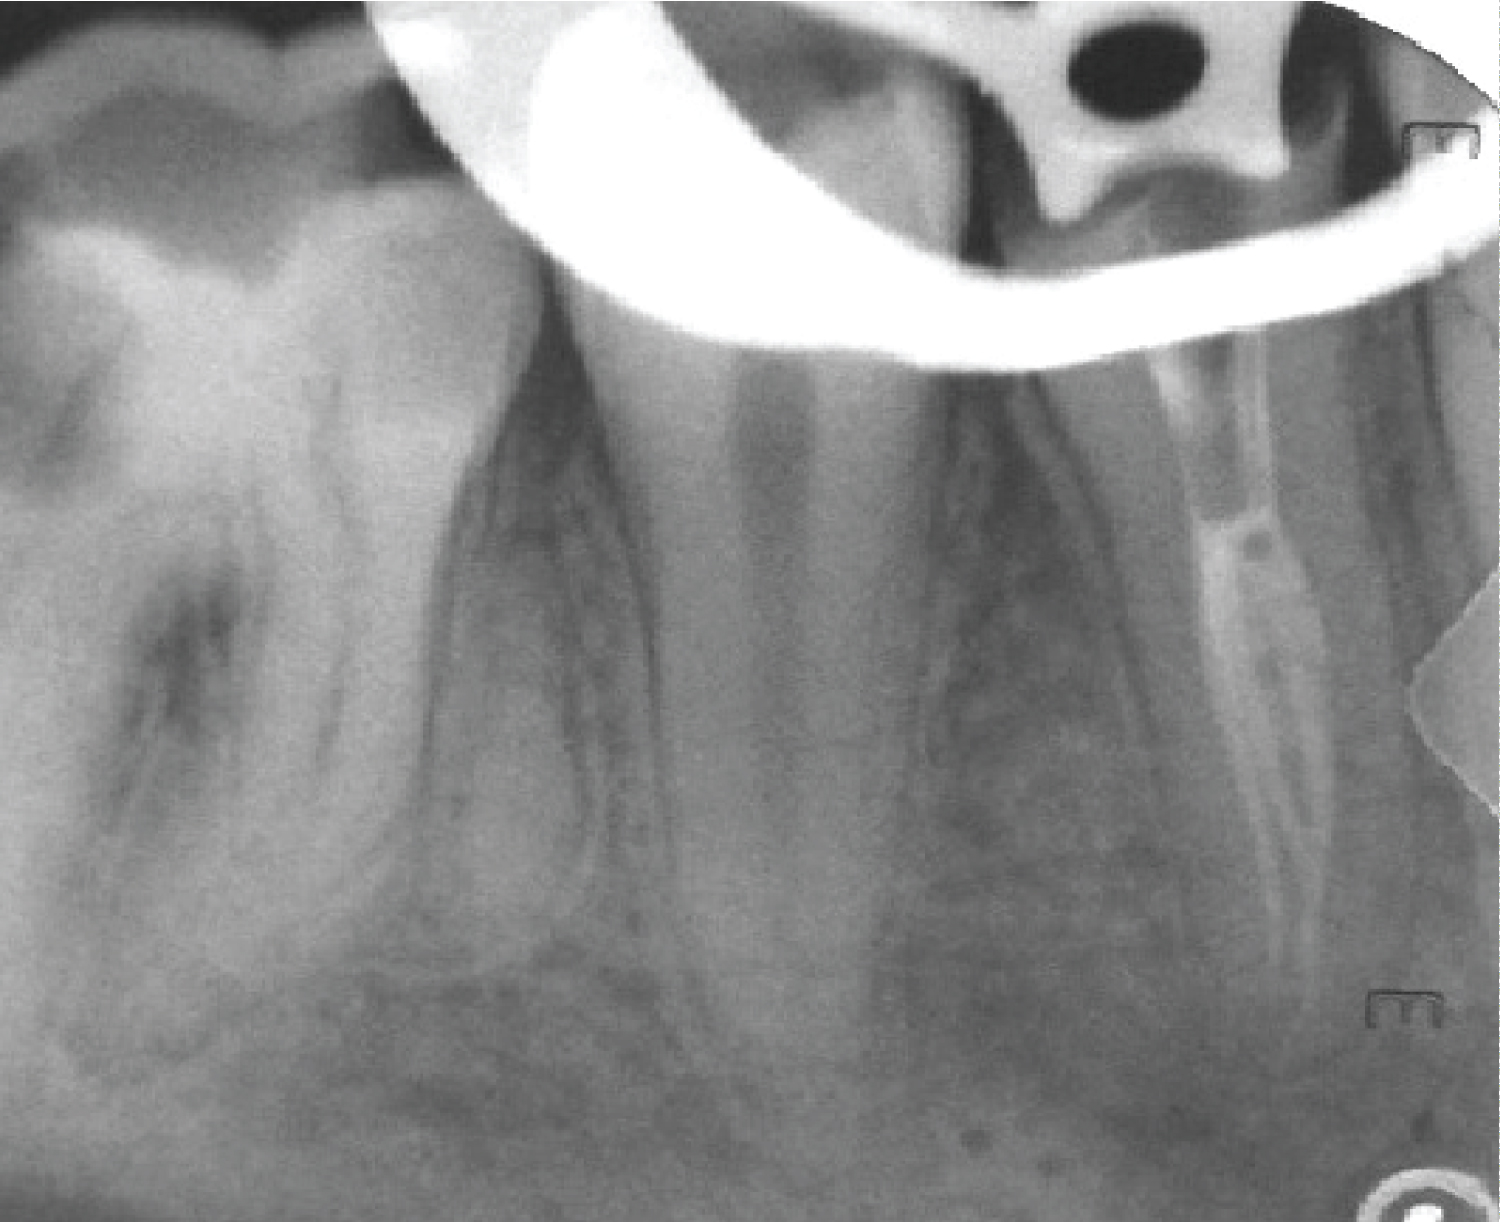

The clinical examination revealed a carious mandibular right first premolar and first molar. Tooth #44 and #46 were not mobile, and periodontal probing was within physiological limits. The cold test revealed a lingering response with tooth #44 and a normal response with tooth #46, and both teeth were not tender on percussion. A preoperative radiograph revealed coronal radiolucency approaching the pulp of tooth #44. Furthermore, the fast break phenomenon indicated the presence of division of the main canal into more than one canal at the middle root level (Figure 1). A diagnosis of symptomatic irreversible pulpitis with normal periapex was made, and nonsurgical root canal treatment was planned based on the clinical and radiographic findings. The treatment plan was discussed with the patient, and the patient signed the consent form.

Figure 1: A preoperative periapical radiograph of tooth #44. View Figure 1

A sudden narrowing of the root canal space known as “the fast break phenomena” indicates its division into two or more canals [2,15]. This was evident in both cases preoperative radiographs. Pulp chamber map analysis with the aids of the magnifying loupes helps in locating all the root canals.